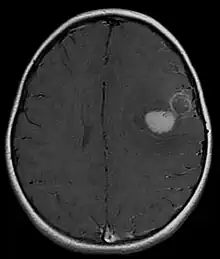

Several analysis can be used to determine the presence of the disease. Physical examinations showing papilledema, visual field defects, cranial nerves palsy, dysphasia, and focal neurological deficits are evidences for possible tumor.[2] PNETs can also be spotted through computed tomography (CT) and magnetic resonance imaging (MRI).[2] In images produced by MRIs, an irregular augmentation among a solid mass will indicated the presence of tumor.[3] However, the results of MRIs are usually ambiguous in defining the presence for this specific tumor.[2] In CT scans, the presence of PNETs will be indicated by an elevated density and an increase in volume of the brain.[2] The CT scan can also show calcification,[3] which is present in 41-44% of PNET cases.[2] Since the tumor can be replicated in other parts of the nervous system through the cerebrospinal fluid (CSF), a CSF analysis can also be conducted.[2] A spinal MRI is a fourth type of analysis that is useful in investigating the level of tumor propagation to the spinal cord.[2]